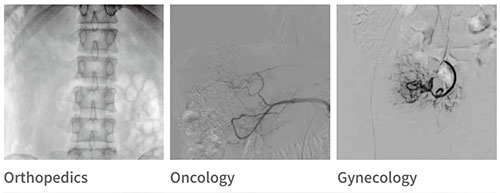

Interventional Department

PLX7100A is widely used in clinical applications and is suitable for interventional

operations in various departments.

Gastroenterology